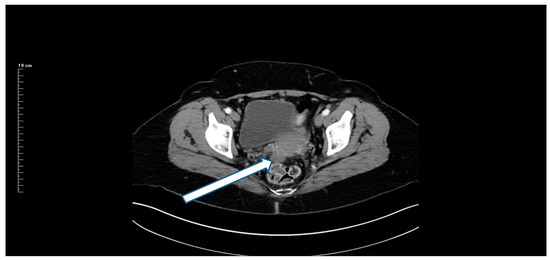

13 December 2017: Preoperative CT showed an 8 cm mass (Figure 1).

Figure 1. CT of a right-sided primary colonic mass that measures 8 cm in its greatest dimension. The external surface of the mass is irregular, suggesting peritoneal thickening. The medial aspect of the mass abuts the duodenum and no fat plane separating the mass from the second portion of the duodenum is evident. The mass penetrates posteriorly toward the right common iliac artery without obvious obstruction of the right ureter. A fat plane between the posterior aspect of the mass and the psoas muscle is present. No obstruction or perforation of the bowel above the mass exist. A single 1.5 cm lymph node is enlarged at the medial aspect of the mass. No additional systemic or local–regional manifestations of the cancer are evident. Radiologically, the mass is staged as T3/T4, N1, M0 with transmural extension through the wall of the intestine.